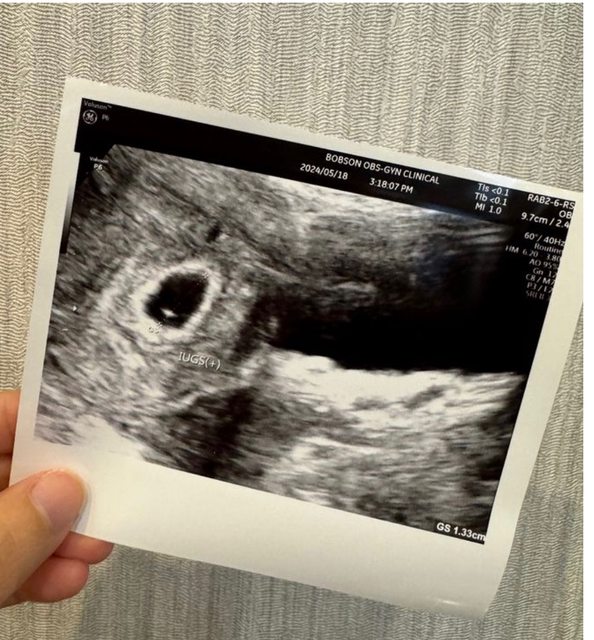

各位爸爸媽媽好, 我上一次月經第一天是3/25, 5/4去照超音波看到約0.56的胚囊, 5/18去照超音波看到約1.33的胚囊,但還沒看到胚胎,按照孕期計算這週應該是第七週, 但醫生說可能才五週多一點,醫生說下週一定要看到胚胎。 請問爸爸媽媽誤差的兩週是正常嗎, 我好緊張喔QQ https://i.imgur.com/86HaV2s.jpeg

n870881 : 我第一次照也是誤差約兩週喔 過兩週照到心跳就校正 05/22 19:57

n870881 : 回歸了 現在10週了寶寶很健康~ 05/22 19:57

lalatwo : 我第二次看診也是應該8週但照出來才6週,後來一週後 05/22 20:08

lalatwo : 回診照到,後續大小也慢慢追上,目前13週已經跟app 05/22 20:08

lalatwo : 推估時間一樣 05/22 20:08